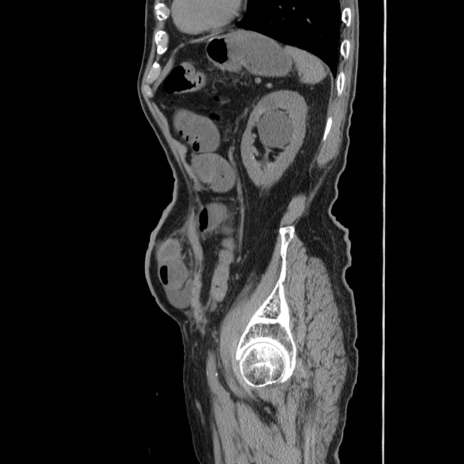

症例24(矢状断像)

【症例】80歳代男性

【主訴】左側腹部痛、嘔吐

【現病歴】本日早朝より左腹部に痛みあり。昼頃嘔吐認めたため、救急要請。

【既往歴】直腸癌(Mile手術)、胆摘

【身体所見】意識清明、BT 35.9℃、BP 221/93mmHg、SpO2 97%(RA) 、腹部:左ストーマ周囲に限局性の腹部膨隆あり。 膨隆部自発痛・圧痛あり・軟。

【データ】WBC 7700、CRP 0.09